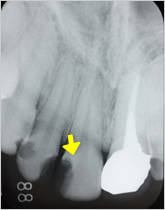

感染根管処置症例.2

主訴:前歯に違和感がある。

- 過去に根管治療を行っていたが、感染を起こし根の先に大きな膿の袋が出来ている。

- 再度根管治療を行い、根の内部から膿の袋に直接薬を作用させている。

- 根管充填剤が根尖(根の先端)まできっちりと充填されている。術前に存在した大きな膿の袋は消失してきている。